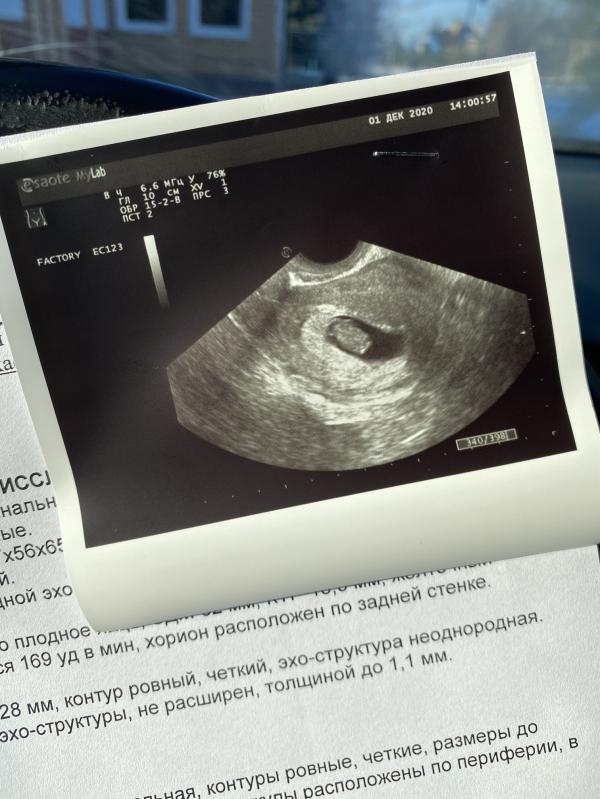

Увидев на вашем фото 169 ударов, подумала что девочка))